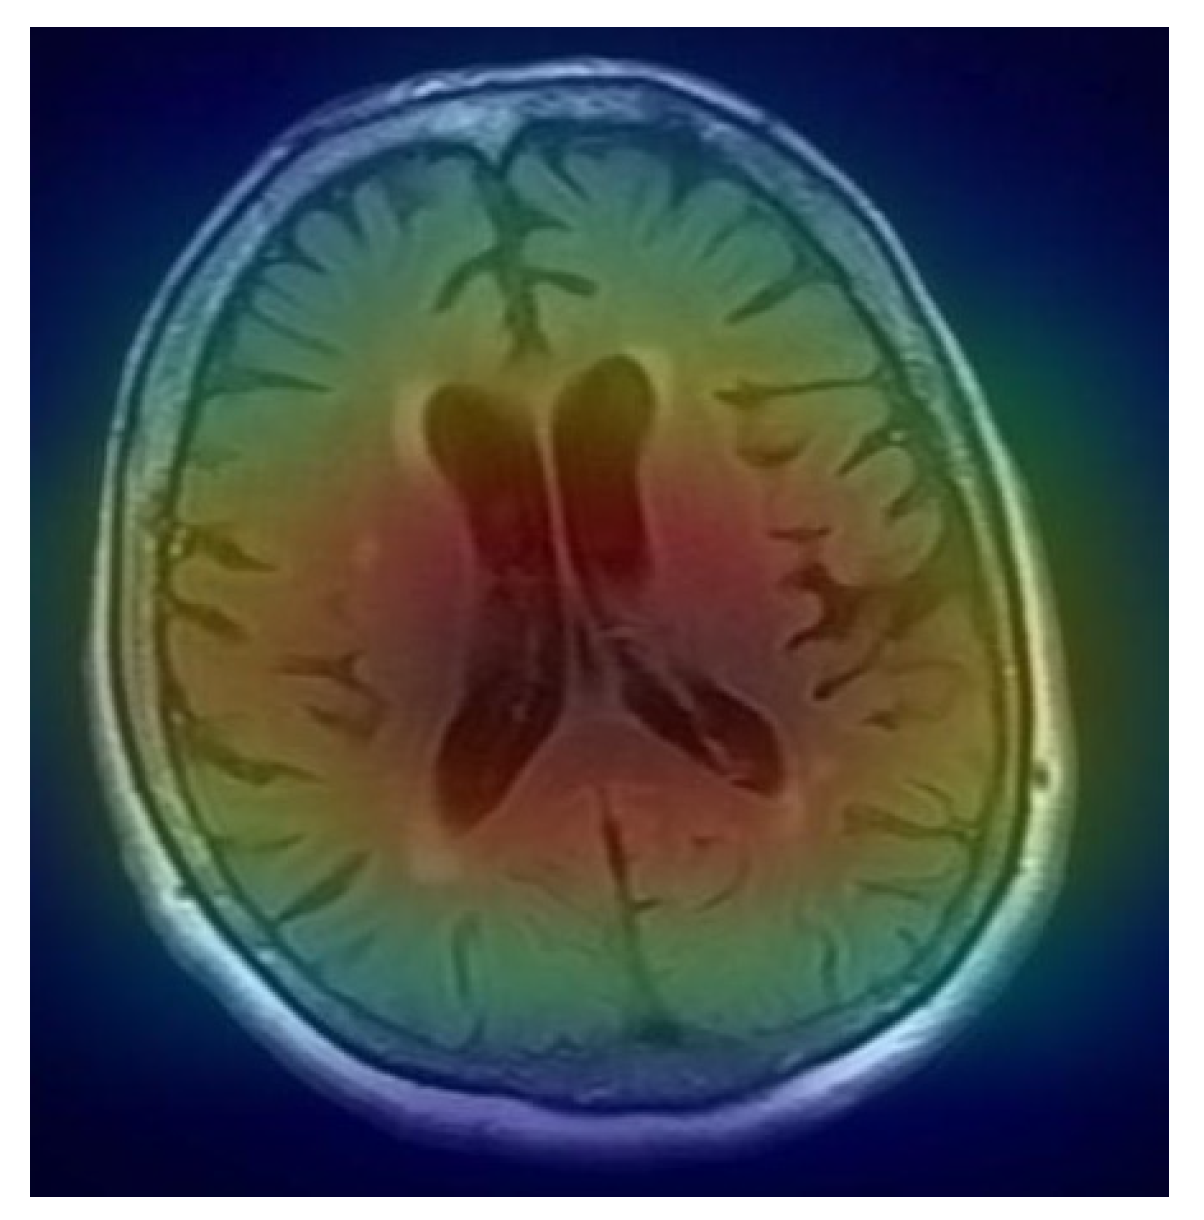

After completing the prediction process, the convolutional neural network (CNN) model generates a heatmap visualization, providing an interpretable overlay for the classified MRI image. This heatmap highlights the areas within the MRI scan that contributed most significantly to the model's decision, effectively revealing the model’s focus and rationale in making its prediction. By emphasizing specific regions within the MRI image, the heatmap aids in understanding the model's interpretation of the visual data, which is particularly valuable in clinical and diagnostic contexts.

Figure 8. The heat-map of predicted image.

The heatmap is subsequently masked with the original MRI image, combining both layers into a single output. This overlay technique enhances visual comprehension by aligning the highlighted features from the heatmap directly with the anatomical structures in the MRI scan. The combination of the original image and the heatmap visualization provides medical practitioners or researchers with a clearer view of which parts of the brain were instrumental in the model's classification, such as identifying normal or abnormal tissue patterns.

By producing this layered output, the model assists in bridging the gap between complex neural network decisions and human interpretability. This masking process not only enhances transparency but also builds confidence in the model's predictions, as it visually confirms that the CNN is focusing on medically relevant regions within the MRI. Such interpretability methods are essential in healthcare applications, where understanding the underlying basis of AI-driven predictions is crucial for informed decision-making.